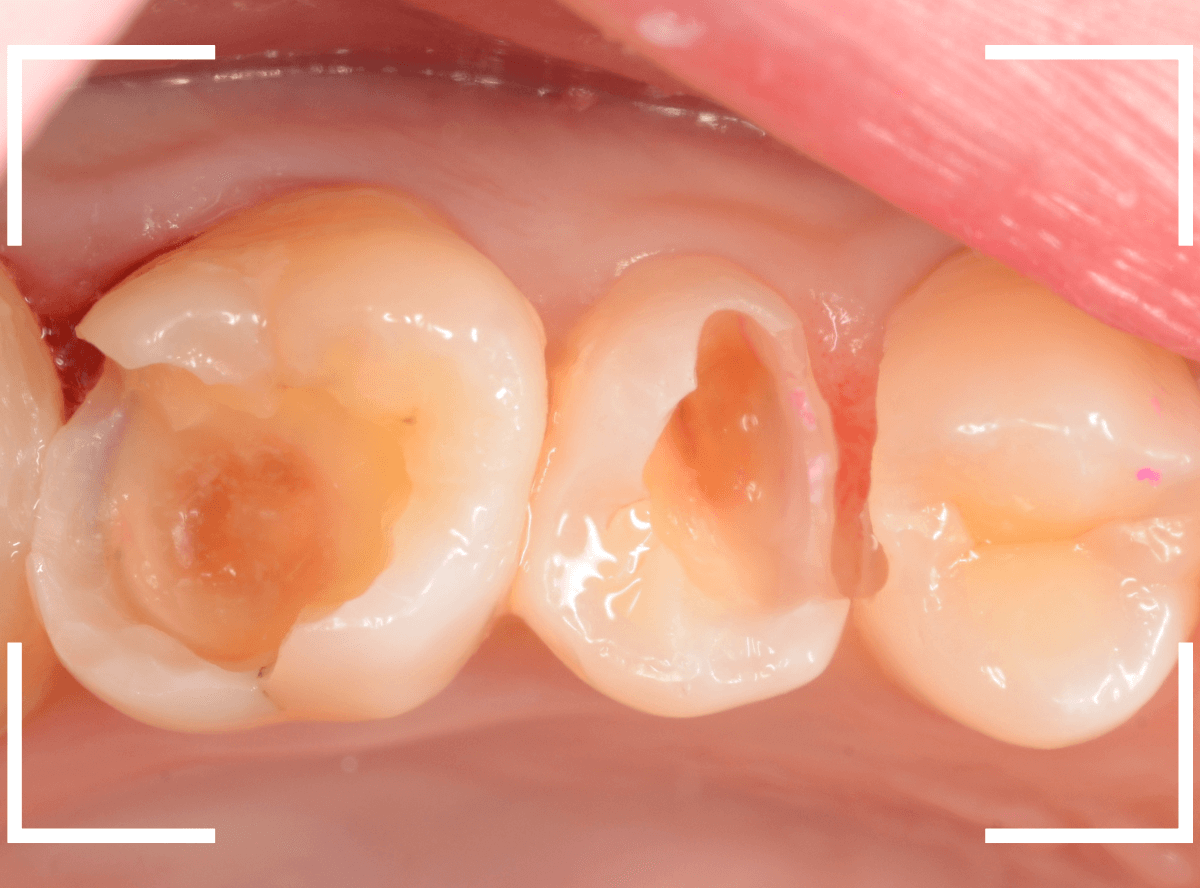

舌のそばの虫歯とセラミック治療

下の奥歯が虫歯になった患者さんのケースです。

〇部が虫歯の部分です。

写真で見てわかるように、常に舌が歯に触っているような状況です。

このような場合、虫歯を見つけづらいですし、治療の難易度もあがります。

虫歯の治療を開始します。

隣の歯とのすき間を中心に広い虫歯になっていました。

虫歯治療後、特に症状もなく経過観察できましたので、つめものを作る治療に入ります。

セラミック治療をご希望されましたので、

小臼歯をE-MAX・インレー、

大臼歯をジルコニア・インレーで処置することになりました。